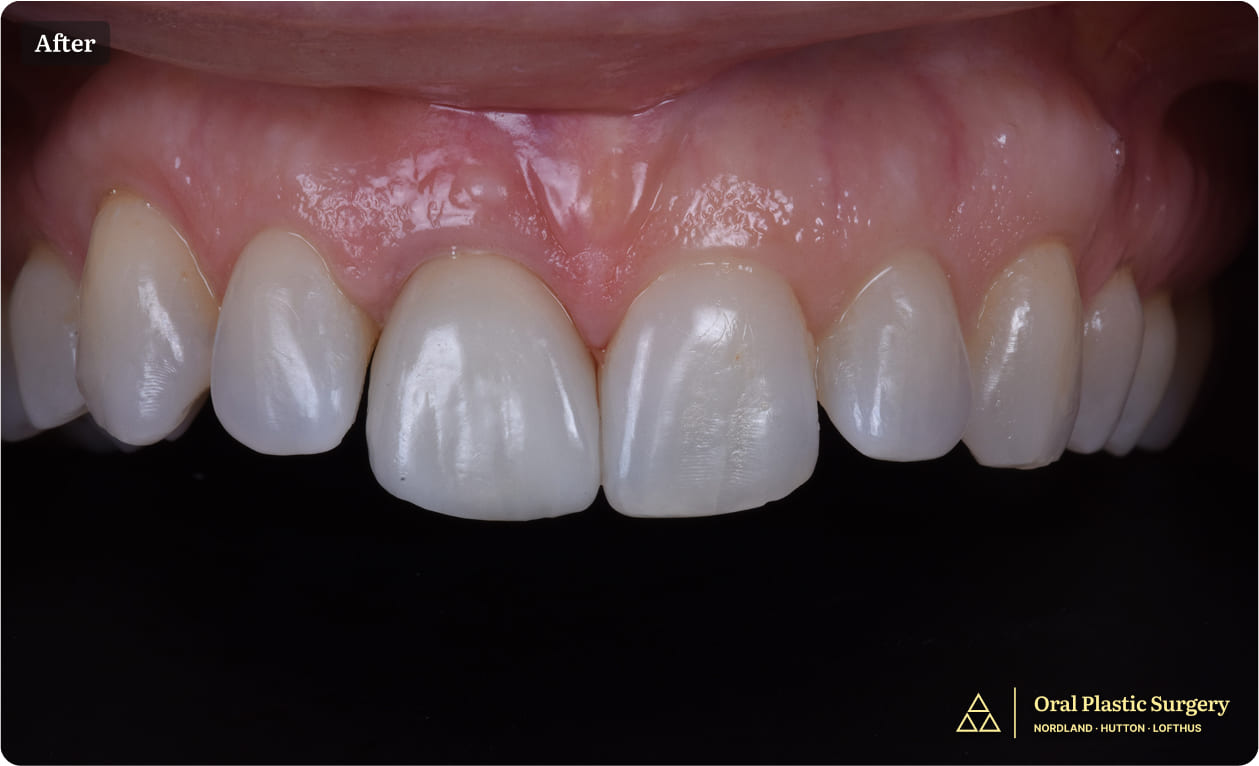

Showing the completed restoration with a natural and seamless appearance

Because of the careful implant placement and ridge augmentation, the final crown mimicked the natural tooth in both shape and gum contour. The gumline emerged naturally around the new tooth, blending flawlessly with adjacent teeth.